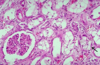

What do you see here?

Acute interstitial nephritis